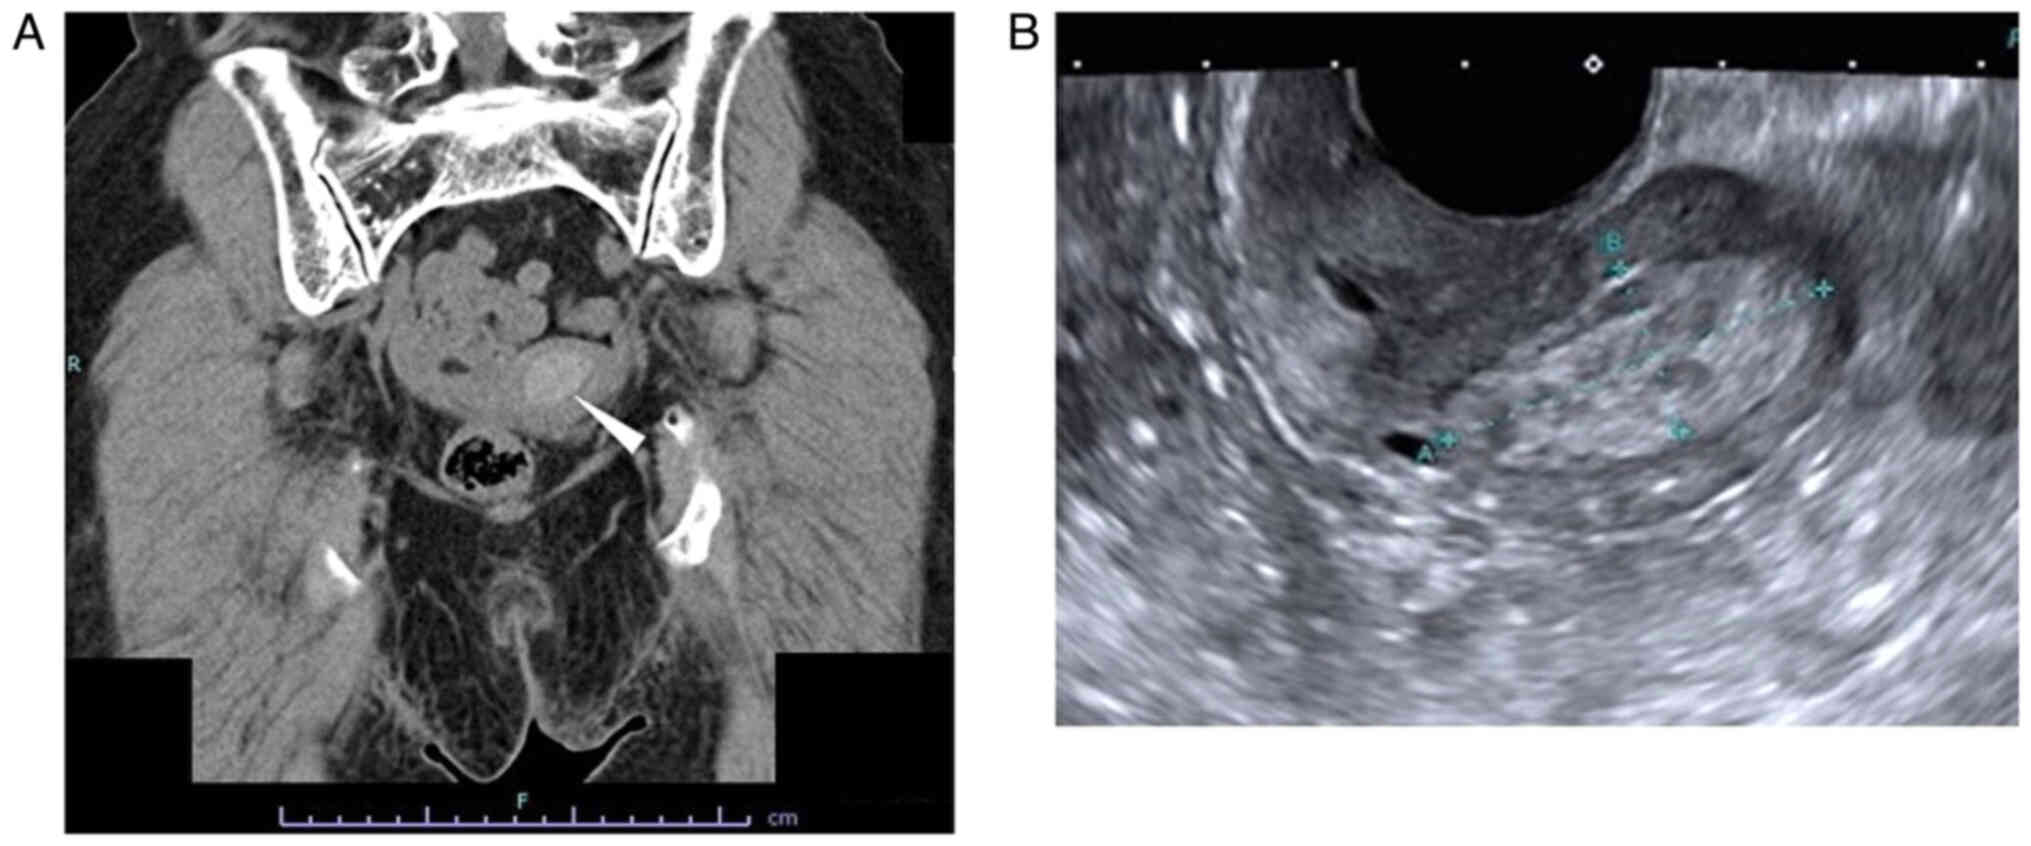

The patient was an 80-year-old gravida 4 para 3 female who had experienced menopause around the age of 50 years. The patient had undergone an appendectomy at age 13 and surgery for rhino polyps at age 74. In addition, the patient had received surgery and radiotherapy for vulvar Paget's disease at the Department of Dermatology of Osaka Metropolitan University Hospital (Osaka, Japan) at age 79. Regarding the family history of the patient, the brother of the patient had gastric cancer. After the surgery (tumorectomy) and radiotherapy (radiation dose, 60 Gy; fractionation, 30) for vulvar Paget's disease, the patient was followed up at the outpatient department of the Department of Dermatology, where a uterine tumor was accidentally identified by CT (Aquilion ONE; Canon, Inc.) 1 year after surgery (Fig. 1A). Therefore, the patient was referred to the Gynecological Department of Osaka Metropolitan University Hospital (Osaka, Japan). The patient experienced no subjective symptoms, such as abnormal genital bleeding or abdominal pain. A vaginal examination revealed uterine bleeding that was unremarkable and not abnormal. Transvaginal ultrasonography (Aplio a450; Canon, Inc.) showed a high-intensity mass in the uterine cavity (Fig. 1B). Tumor markers revealed that the serum levels of carcinoembryonic antigen (CEA) measured using CEA Abbott Alinity G06290R04, carbohydrate antigen (CA)19-9 measured using CA19-9 XR Abbott Alinity G06327R03, CA125 measured using the CA125 II Abbott Alinity G06330R04 (all from Abbott Molecular Inc.) and sialyl-Tn measured using the STN Otsuka RIA kit (Otsuka Assay Laboratories) (all measurements taken according to the manufacturer's instructions) were within normal ranges as follows: CEA <1.7 ng/ml (normal range, ≤5.0 ng/ml); CA19-9, 3 U/ml (normal range, ≤37.0); CA125, 16 U/ml (normal range, <35.0 U/ml), sialyl-Tn, 16.0 U/ml (normal range, ≤45.0), with blood tests indicating no other abnormal findings. MRI revealed a 25×15-mm mass, which was of low intensity in the tumor (T)2-weighed images, but of high intensity in the T1-weighted images (version 3.0; Philips Ingenia). In addition, the mass of the patient had high intensity in the diffusion-weighted images, but low intensity in the apparent diffusion coefficient map, which suggested the presence of a malignant tumor in the uterine cavity. There were no abnormal lesions in the uterine cervix, suggesting that there was no cervical invasion or malignancies of cervical origin (Fig. 2).

Figure 1.

Images of CT scan and trans-vaginal ultrasonography. (A) CT scan. A 25.1×15.2-mm, high-density lesion was detected in the uterine cavity indicated by the white arrowhead (120 kilovoltage peak; quality reference mAsec, 114/200). (B) Trans-vaginal ultrasonography. A 31.2×13.3-mm, high-echoic lesion was detected in the uterine cavity (dynamic range, 65; gain, 89; frame rate, 18 frames per sec).